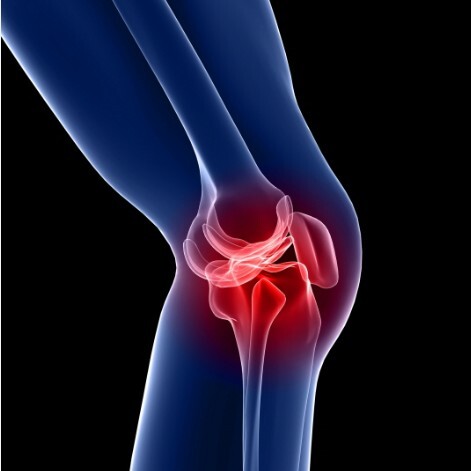

- 관절 통증 및 염증 완화: 옵티머스트에 함유된 성분들은 관절 통증을 완화하고 염증을 줄이는 데 도움을 줍니다. 그루코사민과 콘드로이틴은 연골 조직을 보호하고 재생을 촉진하여 관절 통증을 완화시키는 역할을 합니다.

- 연골 보호 및 재생: 옵티머스트는 연골 조직을 보호하고 재생하는 데 도움을 주는 성분들을 함유하고 있습니다. 그루코사민은 연골 세포의 활동을 촉진하여 손상된 연골을 회복시키고, 콘드로이틴은 연골 조직을 구성하는 단백질 성분으로 연골의 탄력과 강도를 유지합니다.

- 관절 윤활 및 움직임 개선: 옵티머스트는 관절을 윤활시켜 움직임을 원활하게 만드는 역할을 합니다. 그루코사민과 콘드로이틴은 습관성 관절액을 생성하여 관절 표면을 윤활시키고 마찰을 줄여줍니다.

- 관절 건강 유지: 옵티머스트의 성분들은 관절의 건강을 유지하는 데 도움을 줍니다. 그루코사민과 콘드로이틴은 연골 조직의 강도와 탄력을 유지하며, 관절의 안정성을 높여 손상을 예방합니다.

- 뼈 및 연조직 강화: 옵티머스트는 뼈 및 연조직의 강화에도 도움을 줍니다. 그루코사민과 콘드로이틴은 뼈와 연조직의 형성에 필요한 성분으로 작용하여 강력하고 건강한 뼈와 연조직을 유지하는 데 도움을 줍니다.